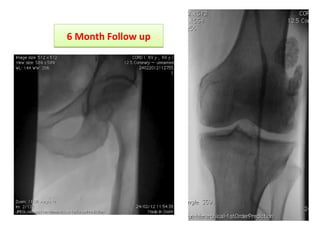

66 MMoonntthh FFoollllooww uupp

Clinical outcome •Dischargedat home on day 4 (Serum creatinine Back to baseline) •Medical therapy was tuned for CAD •DAPT for 30 days •Healed Ulcer after 3 weeks